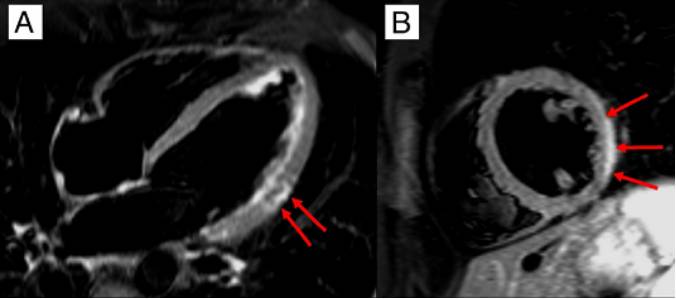

心脏磁共振

最重要的无创性检查方法,显示3种心肌病变

诊断准确性:符合2-3个标准时达78%,仅LGE时68%发病7天后MRI敏感性高于发病初期

指导心肌活检部位

路易斯湖MRI诊断标准

CMR显示的组织特点

水肿和/或典型的心肌炎LGE。